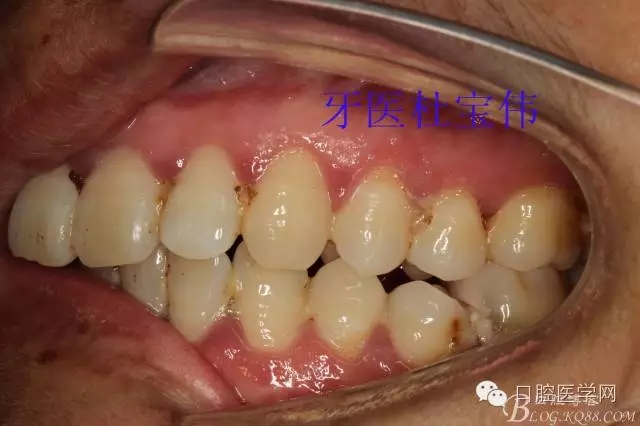

病例二術(shù)前照片